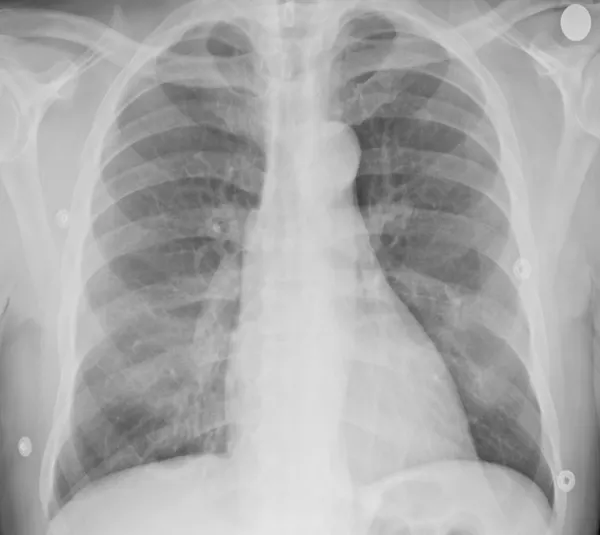

Se recurre a esta técnica de imagen porque, debido a la afectación primaria del sistema respiratorio, la infección por SARS-CoV-2 deja evidencias radiológicas de neumonía visibles bajo los rayos X. Concretamente, la neumonía asociada a la covid-19 produce sombras en los pulmones conocidas como opacidad de vidrio esmerilado. Estas opacidades suelen aparecer con una distribución periférica o posterior, principalmente en los lóbulos inferiores y con menos frecuencia en el lóbulo medio derecho.

En los dos primeros días de la infección, el 50% de los pacientes de covid-19 ya muestra lesiones pulmonares parenquimatosas, superando el 90% entre los 3 y 5 días. Lo sorprendente es que esto ocurre incluso en pacientes asintomáticos. Por ello, complementar la RT-PCR con una radiografía de tórax mejora la sensibilidad en el diagnóstico, reduciendo significativamente el número de falsos negativos. Es importante porque los falsos negativos son precisamente el talón de Aquiles de la prueba RT-PCR, cuya sensibilidad oscila entre el 70-90%. Otra ventaja importante es que la radiografía está lista en cuestión de minutos.